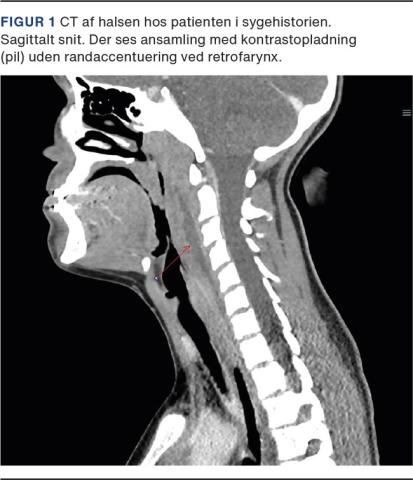

En 13-årig tidligere rask pige blev henvist til en øre-næse-hals-afdeling på mistanke om peritonsillær absces. Hun havde over fire dage haft tiltagende feber, hovedpine, ensidige øresmerter og kraftige synkesmerter. Ved en objektiv undersøgelse fandtes hun akut påvirket og højfebril med en temperatur på 40,0 °C. Desuden havde hun bilateral cervikal lymfadenopati. Der blev ikke fundet trismus, og tonsillerne havde hverken belægninger eller hypertrofi. En fiberlaryngoskopi viste ingen overbevisende tegn til infektion i svælg eller strube. Uagtet de sparsomme fund blev hun, foranlediget af almenpåvirkningen, indlagt til smertebehandling og i.v. givet bredspektrede antibiotika. En CT med kontrast af halsen viste en aflang retrofaryngeal opladning, der målte 87 × 25 × 7 mm (Figur 1). Grundet mistanke om absces blev der foretaget kirurgisk spaltning retrofaryngealt, men der kunne ikke påvises en ansamling, hvorfor opladningen blev tolket som værende ødembetinget.